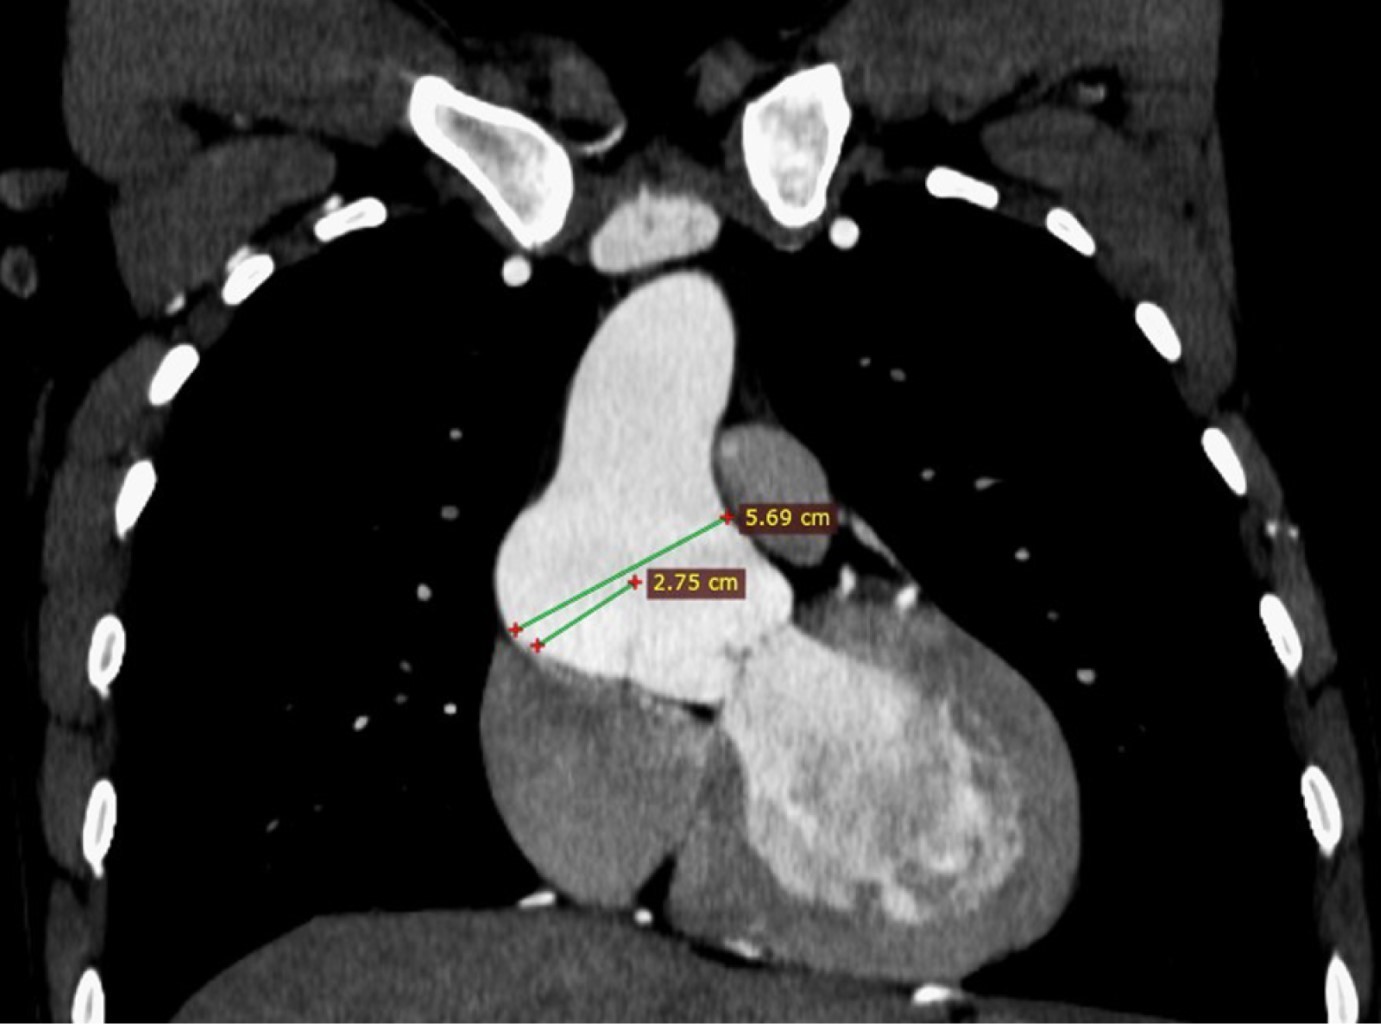

Coartación aórtica asociada a válvula aórtica bicúspide complicada con aneurisma aórtico postdisección

Sánchez-Amaya DJ, Godínez-Córdova LB, López-Lizárraga MÁ, Araiza-Garaygordobil D, Arias-Mendoza A

coartación aórtica, disección aórtica crónica, aneurisma aorta ascendente, válvula aórtica bicúspide.

La coartación aórtica es un trastorno congénito que afecta no solamente a la aorta, sino que también puede asociarse a válvula aórtica bicúspide y predispone a síndromes aórticos. Se reporta el caso de un paciente de 28 años de edad con hipertensión secundaria debido a coartación aórtica postductal asociada a válvula aórtica bicúspide que a su vez presentó disección crónica de la aorta ascendente. La coexistencia de enfermedad valvular aórtica, así como múltiples condiciones aórticas, es una situación rara que requiere una evaluación altamente especializada para garantizar un resultado favorable. El tratamiento se estableció en dos fases: aortoplastia con colocación de stent y luego cirugía de reemplazo aórtico y valvular, con una recuperación favorable.

Figura 3